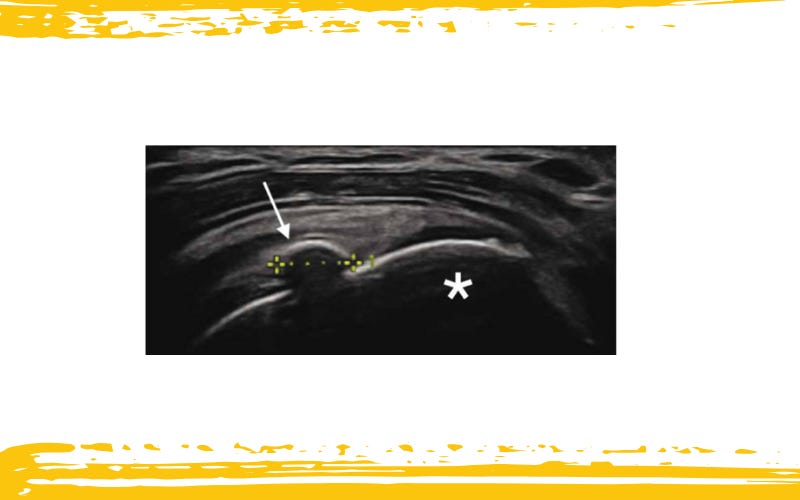

Rotura completa de la cabeza larga del bíceps (LHBT).

El corte transversal en eje corto (A) a nivel del surco bicipital muestra derrame anecoico y hemorragia dentro de la vaina sinovial (flecha).

El corte en eje largo (B) muestra un derrame abundante con engrosamiento de la pared de la vaina (flecha).

En ninguno de estos niveles se identifican fibras tendinosas, observándose el vientre muscular y el muñón distal retraídos inferiormente.

Engrosamiento anecoico (flechas) de la vaina del tendón de la porción larga del bíceps en un caso de tenosinovitis.